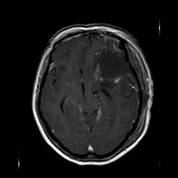

经家属同意后,医生决定栓塞肿瘤近端的供血动脉,并于当天行左侧中颅窝占位病变切除术;术中可见肿瘤灰红色,有假包膜,分块切除肿瘤;由于术前行介入栓塞,术中可见血供明显减少,且出血少,左侧大脑中动脉及左侧大脑前动脉被肿瘤压迫移位,医生给予保护后将肿瘤全切除。术后黄女士恢复顺利,已痊愈出院。病理结果显示:脑膜瘤,合体细胞型,WHO I级。

术后复查MRI可见肿瘤全切